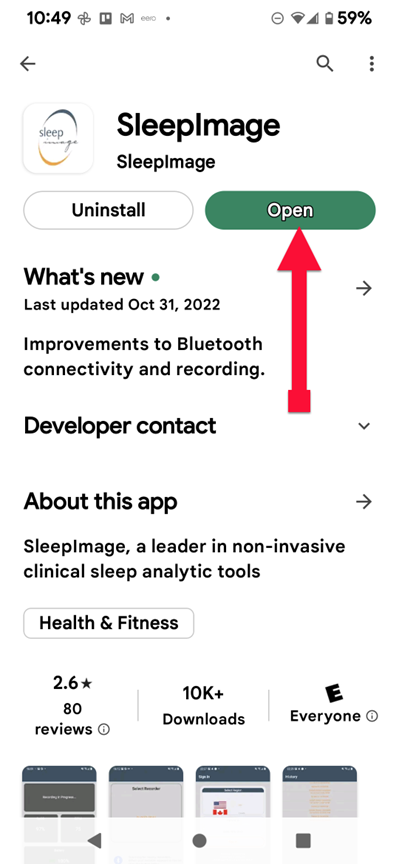

SLEEPIMAGE APP (Android)

SLEEPIMAGE APP (Android)

SLEEPIMAGE APP (Android)

SLEEPIMAGE APP (Android)

SLEEPIMAGE APP (Android)

SLEEPIMAGE APP (Android)

SLEEPIMAGE APP (Android)

SLEEPIMAGE APP (Android)

SLEEPIMAGE APP (Android)

SLEEPIMAGE APP (Android)

SLEEPIMAGE APP (Android)

SLEEPIMAGE APP (Android)

SLEEPIMAGE APP (Android)

SLEEPIMAGE APP (Android)

SLEEPIMAGE APP (Android)

SLEEPIMAGE APP (Android)

SLEEPIMAGE APP (Android)

SLEEPIMAGE APP (Android)

SLEEPIMAGE APP (Android)

SLEEPIMAGE APP (Android)

SLEEPIMAGE APP (iPhone)

SLEEPIMAGE APP (Android)

SLEEPIMAGE APP (Android)

SLEEPIMAGE APP (Android)

SLEEPIMAGE APP (Android)

SLEEPIMAGE APP (Android)

SLEEPIMAGE APP (Android)

SLEEPIMAGE APP (Android)

SLEEPIMAGE APP (Android)